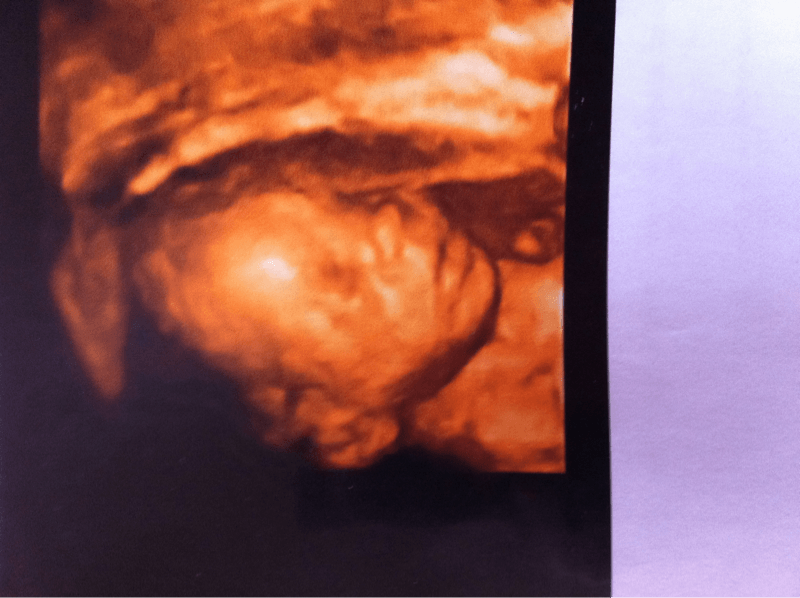

Voilà ct pour ma fille

Pièces jointes

• image-1708265371.png

image-1708265371.png

207.6 KB · Affichages: 32